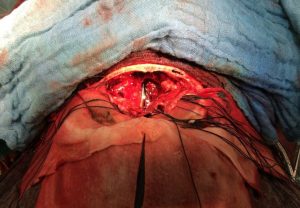

Ο ασθενής υπεβλήθη σε αμφιμετωπιαία κρανιοτομία καθώς επίσης και σε ενδοσκοπική διαρρινική αφαίρεση της βλάβης. Η ιστολογική εξέταση ανέδειξε αισθησιονευροβλάστωμα.

Εικόνα 2: Διεγχειρητική φωτογραφία. Προσέξτε το φώς του ενδοσκοπίου το οποίο μπορεί να παρατηρηθεί από την πλευρά της κρανιοτομίας.